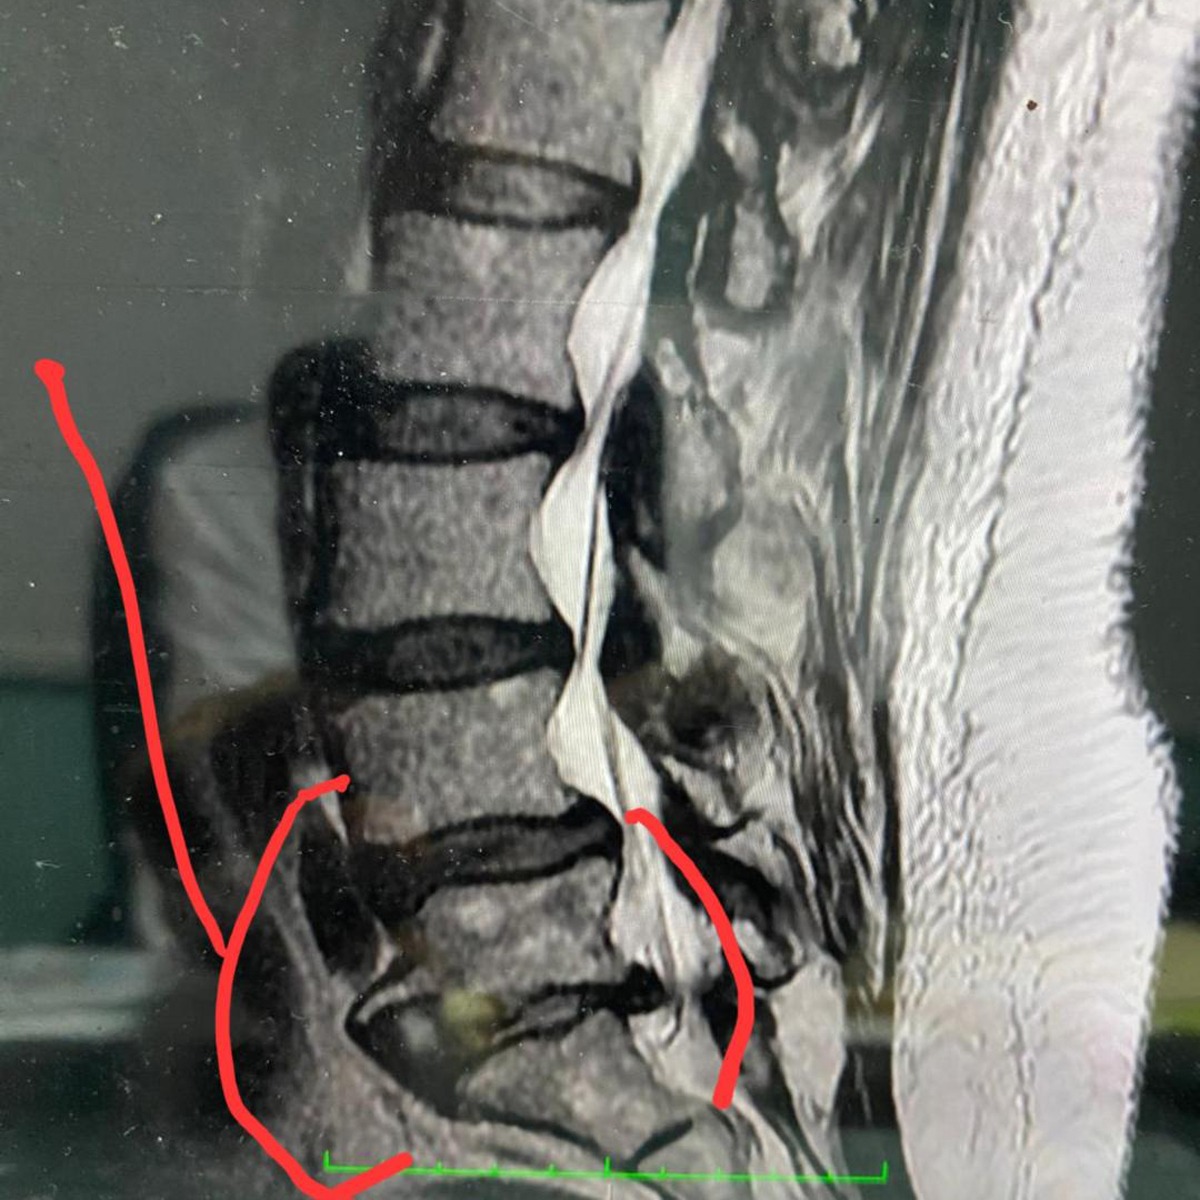

Recently, she suffered a serious fall that fractured her coccyx and caused damage to her lower spinal vertebrae. She was hospitalized in extreme pain, and is now facing major surgery and extensive physical therapy to heal and regain full mobility. Unfortunately, a clerical error some time ago caused the cancellation of her medical insurance, leaving her with no coverage for this urgent medical care.